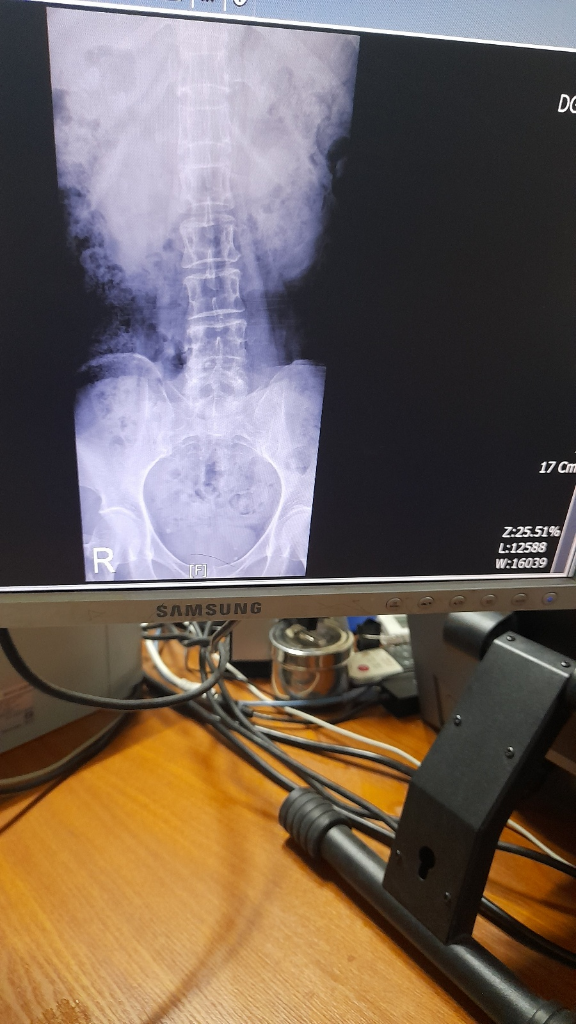

엄마가 한달전부터 허리가 너무 아프다고 하셔서 mri를 찍었는데 촬영한 병원소견상으로는 이 정도로 허리가 그렇게 아플리 없다고 했다고 합니다.

정형외과를 다른데 가봐야 하는지 궁금해서 질문 드립니다. 답변주시면 정말 감사드리겠습니다.

보여주신 사진은 x-ray 와 CT로 보이는데, 큰 특이소견이 있어 보이진 않습니다. 하지만 CT는 한장만 보는 것이 아니라 수십, 수백장의 사진을 보는 것이기 때문에 한 단면만 보는 것은 의미가 없으므로 전체 영상이나 판독지를 확인해보시는 것이 좋겠습니다.